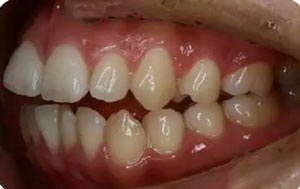

—上中線左偏,下中線右偏

—咬合平面右低左高

—前牙開(kāi)合

—右側(cè)磨牙近中關(guān)系,尖牙遠(yuǎn)中關(guān)系

—左側(cè)磨牙遠(yuǎn)中關(guān)系,尖牙近中關(guān)系

—前磨牙區(qū)及前牙區(qū)均為開(kāi)合

—右側(cè)自第一磨牙開(kāi)始至側(cè)切牙均為反合

上牙弓:尖圓形,25腭側(cè)完全錯(cuò)位,26前移

下牙弓:卵圓形,下前牙區(qū)擁擠